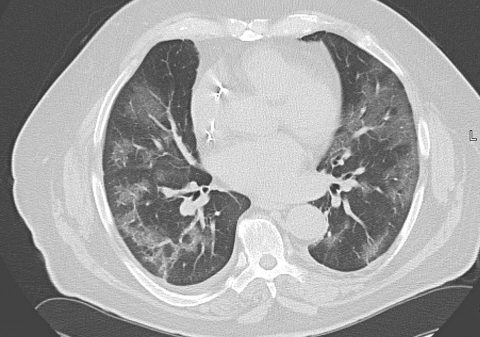

Die vorläufigen Ergebnisse zeigen, dass die Patientinnen und Patienten in der Post-COVID-Sprechstunde vor allem mit Fatigue, Leistungsminderung, Dyspnoe, Konzentrationsstörungen und Schlafproblemen vorstellig werden. Psychische Begleitsymptome sind häufig, besonders finden sich Hinweise auf Depression, Somatisierungs- und Angststörungen. Die apparative Diagnostik zeigt in den meisten Fällen unauffällige Befunde. Dies unterstreicht die bekannten Schwierigkeiten in der Diagnostik. Zur Einordnung der wehrmedizinischen Relevanz erfolgte außerdem eine Datenbankabfrage von Eintragungen der Krankenkarten im Institut für Präventivmedizin der Bundeswehr für die Jahre 2017–2022. Hier zeigt sich ein Aufstieg der ICD U 09.9! (Post-COVID-19-Zustand) auf Platz 3 der Erkrankungen mit langer Krankschreibungsdauer von > 28 Tagen im Jahr 2022.